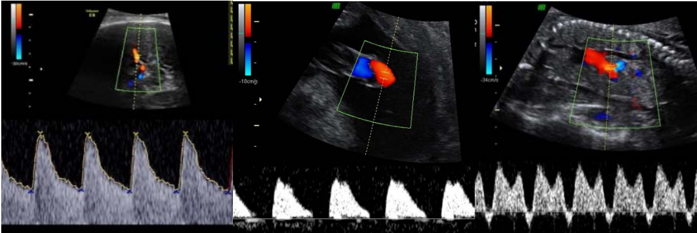

Gestante 28 anos, secundigesta (parto vaginal), na 31ª semana de gravidez. Veio à emergência mostrar resultado de ultrassonografia. No momento, assintomática. Ao exame, estado geral bom, dinâmica uterina ausente, batimentos cardiofetais de 128 bpm e altura de fundo uterino de 21 cm. Pressão arterial de 150 x 100 mmHg. Ultrassonografia com maior bolsão de líquido amniótico de 1,0 cm. Peso fetal estimado de 900g (< 3º percentil). Proteinúria de fita de 2+/4+. Abaixo seguem as imagens da dopplervelocimetria da artéria cerebral média, umbilical e ducto venoso, respectivamente.

Assinale a alternativa CORRETA quanto à conduta, baseada nos critérios diagnósticos da International Society for the Study of Hypertension in Pregnancy.